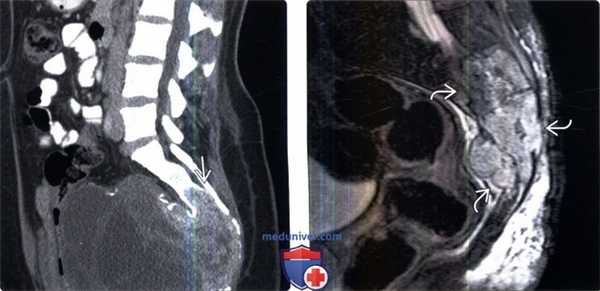

(Слева) Сагиттальный срез, FS Т1-ВИ: крупная ГКО крестца, оттесняющая кпереди прямую кишку. Обратите внимание на тонкие изогнутые линии в толще опухоли, представляющие собой фиброзные или костные перегородки.

(Справа) На сагиттальном Т2-ВИ у этого же пациента отмечается гетерогенная интенсивность сигнала опухоли, хотя в целом его интенсивность невелика. Интенсивность сигнала ГКО вариабельна, что ограничивает информативность этого признака в дифференциальной диагностике.

(Слева) Сагиттальный срез, FS Т1-ВИ с КУ: у этого же пациента визуализируется крупная солидная и гетерогенно контрастирующаяся опухоль, исходящая из крестца. ГКО нередко характеризуется гетерогенным контрастным усилением сигнала.

(Справа) Аксиальный срез, FS T1-ВИ с КУ: картина леченной ГКО, характеризующаяся краевым контрастным усилением сигнала вокруг заполненных жидкостью полостей. Ввиду высокого риска осложнений при тотальной резекции опухолей крестца при данной локализации опухоли применяется химиотерапия, а для оценки динамики процесса и исключения рецидива опухоли проводятся повторные МРТ.

(Слева) Сагиттальный КТ - срез: массивное объемное образование таза, исходящее из нижней половины крестца. Дифференциальный диагноз при подобной картине должен проводиться в первую очередь между хордомой и гигантоклеточной опухолью крестца. Метастатическое поражение маловероятно, поскольку похоже, что данное образование в течение долгого времени практически никак себя не проявляло.

(Справа) Сагиттальный срез, STIR МР-И: злокачественная ГКО крестца В. Признаками, позволяющими заподозрить более агрессивный характер опухоли по сравнению с большинством ГКО, являются более выраженный мягкотканный компонент опухоли и более выраженные деструктивные изменения замыкательных пластинок.